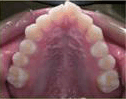

- 矯正治療開始前,

- 要進行一些簡單的常規檢查與記錄,了解口腔與牙齒的情況:

- a. 口內及顏面外觀照相記錄。